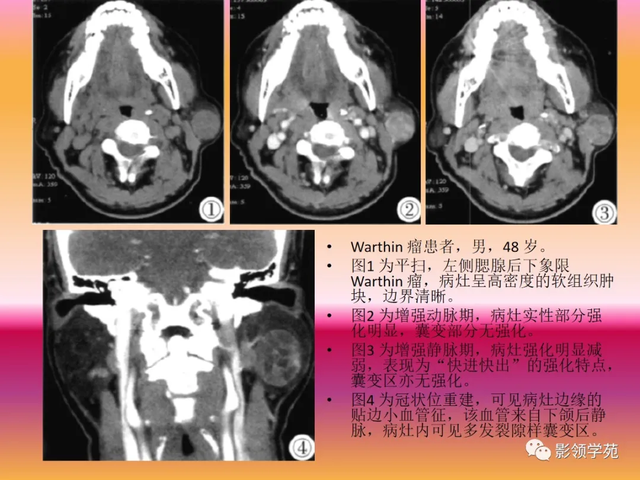

(4)Warthin瘤

腺淋巴瘤:MF,浅叶后下极,双侧多中央

CT体现为囊性病灶,内容物常有分层征象 ,增强扫描囊壁强化显着 。而Warthin 瘤虽可发生囊变坏死,但始终小于实性部门。

病例3:男性,68岁,因“发现右耳垂下肿物30余年”:

病理:腺淋巴瘤

病例4:男性,81岁,因发现右耳下肿物10年余,举行 性增大2年: